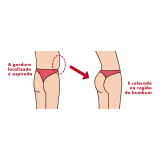

Lipoaspiração a Laser

Você merece a qualidade e comprometimento entregues pela equipe deste consultório médico e se neste momento está à procura de uma equipe que realize lipoaspiração a laser saiba que a FF Cirurgia Plástica disponibiliza de imediato este serviço para você!

Lipoaspiração a laser: atendimento eficiente e com qualidade que você sempre buscou!

Neste consultório médico você encontrará profissionais eficientes e com experiência de excelência. Usufrua de bom atendimento, através dos melhores preços do mercado e de assistência especializada sempre à sua disposição! Leve as suas dúvidas, converse com a equipe da FF Cirurgia Plástica. Contrate bons serviços e sinta-se mais seguro para cuidar da saúde.